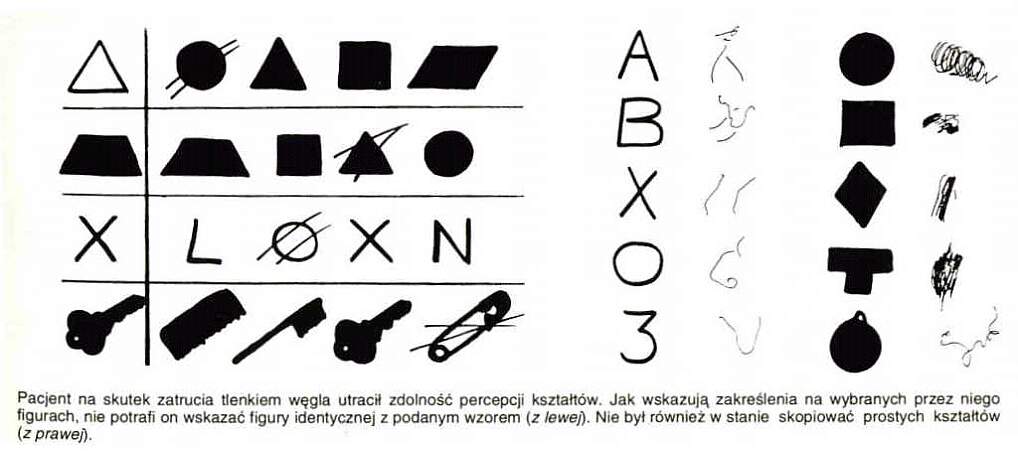

| Uszkodzenia (udary, wypadki, zmiany neurodegenercyjne) obszaru V2 wywołują zaburzoną percepcję kształtów. Agnozja kształtu ma wiele form: |  |

| Agnozja kształtu może być wybiórcza, np. bez prozopagnozji.

Uszkodzenia szlaku do IT i zakrętu kątowego prowadzą do

agnozji wzrokowej, czyli niezdolności do nadania sensu temu co się widzi.

Niemożliwe jest świadome rozpoznania przedmiotów przy zachowanej zdolności do działania, np. uchwycenia przedmiotu czy manipulacji nim (ślepota psychiczna). Zaburzenie dotyczyć może zdolności rozpoznawania obiektów wewnątrz jakiejś kategorii, np. samochodów, krzeseł, zwierząt czy palców ręki. Pomimo prawidłowego wykonania kopii rysunków pacjent nie ma pojęcia, co przedstawiają narysowane przedmioty. |